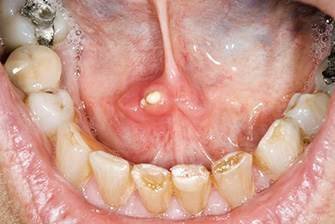

Киста под языком требует оперативного удаления